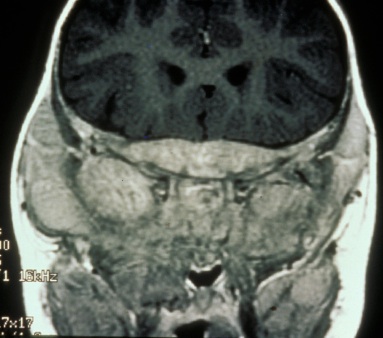

Orbital imaging must be performed on any patient who presents with ocular signs. Orbital metastases tend to occur in the posterolateral orbital wall.[44] Bone destruction may occur, specifically in the lateral orbital wall or sphenoid marrow. On Computed Tomography (CT), metastases can appear as either circumscribed or ill defined, are increased in attenuation compared to muscle, can contain small calcifications, and can invade adjacent structures, including intracranially.[45] On Magnetic Resonance Imaging (MRI), neuroblastoma metastases appear low signal on T1WI, heterogeneous on T2WI due to hemorrhage or necrosis, and heterogeneously enhance post contrast. Tumor extension intracranially and into the adjacent soft tissues may be seen more readily on MR over CT (Figure 3a and b).[46]

Figure 3a. MRI showing tumor along the skull base Figure 3b. Dural and calvarial enhancement from metastases